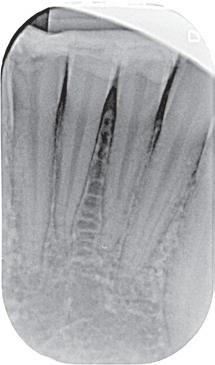

We zijn begonnen met de 13 en hebben een week later de 12 en de 11 behandeld. Bij de 13 kon een volledig necrotische pulpa worden geëxtirpeerd (afbeelding 7). Aangezien we aan de vitaliteit van de 12 en 11 twijfelden, hebben we eerst een proefboring uitgevoerd en beide elementen bleken volledig necrotisch.

De kanalen zijn ultrasoon gespoeld met 2% NaOCl en EDTA onder isolatie van rubberdam. Het kanaal van de 13 is gevuld met MTA (afbeelding 8), omdat er sprake was van een niet-afgevormde radix. Dit is afgedekt met een laagje Vitrebond. In de 12 en 11 hebben we guttapercha en AH26 aangebracht via een hybride vultechniek (afbeelding 9).